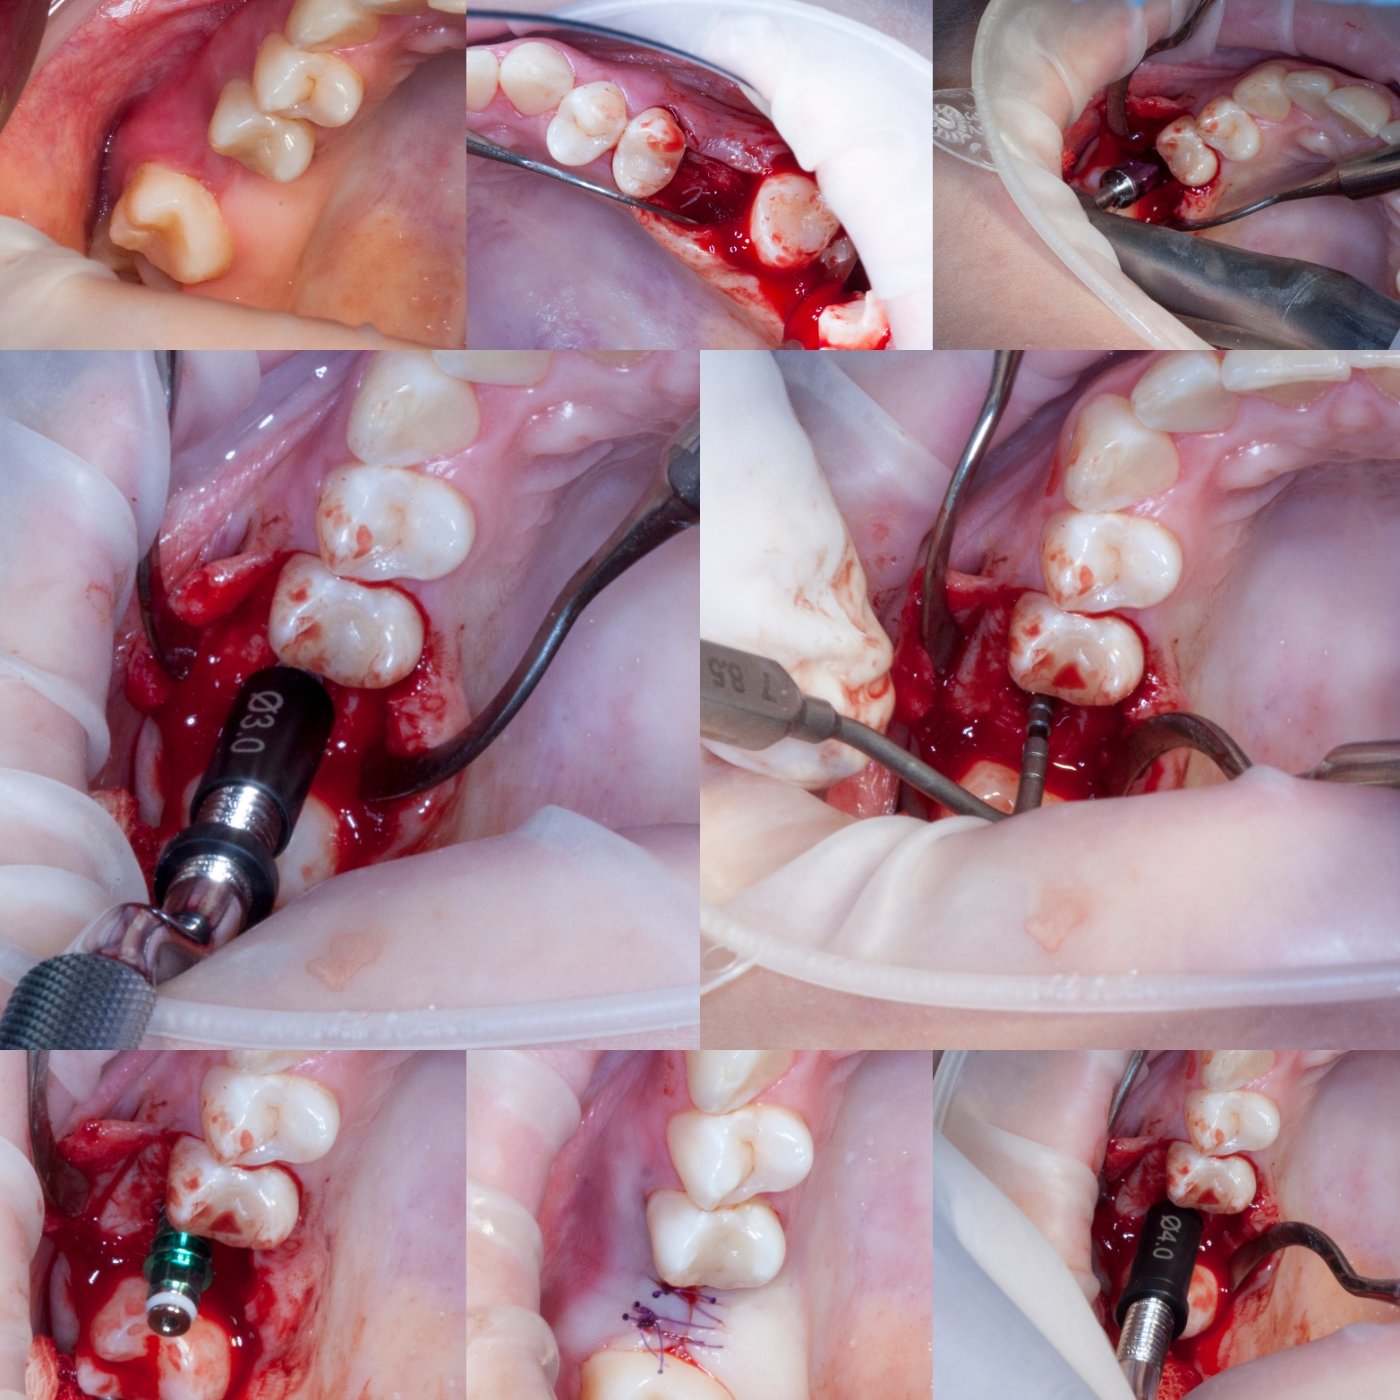

Имплантацией занимаюсь с 2013 года, преимущественно с корейскими системами имплантатов Dentium, Osstem.

Так же есть опыт в установке израйльских имплантатов Noris, Mis, Alpha Bio, и швейцарских имплантатов SIC.

Из навыков: открытый и закрытый синус лифтинг, одномоментная имплантация , расщепление альвеолярного гребня, sausage technique и другая направленная костная регенирация, опыт в работе с титановыми сетками на имплантатах Osstem система Smart Builder, мягкотканная пластика десны, пародонтологические операции. Удаление зубов любой сложности, чтение клкт (3D) и составления рационального плана лечения, стремление расти и развиваться профессионально!